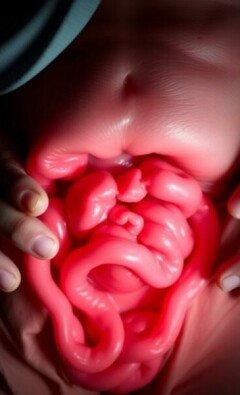

La microbiota y la apendicitis: lo que los estudios nos están revelando y lo que aún falta por entender

Nuevos protocolos para el manejo de la apendicitis no complicada: una guía práctica y humana

Uso de la inteligencia artificial en el diagnóstico de apendicitis: una guía conversacional para entender el presente y el futuro

Avances en técnicas de cirugía laparoscópica: hacia operaciones más seguras, precisas y humanas